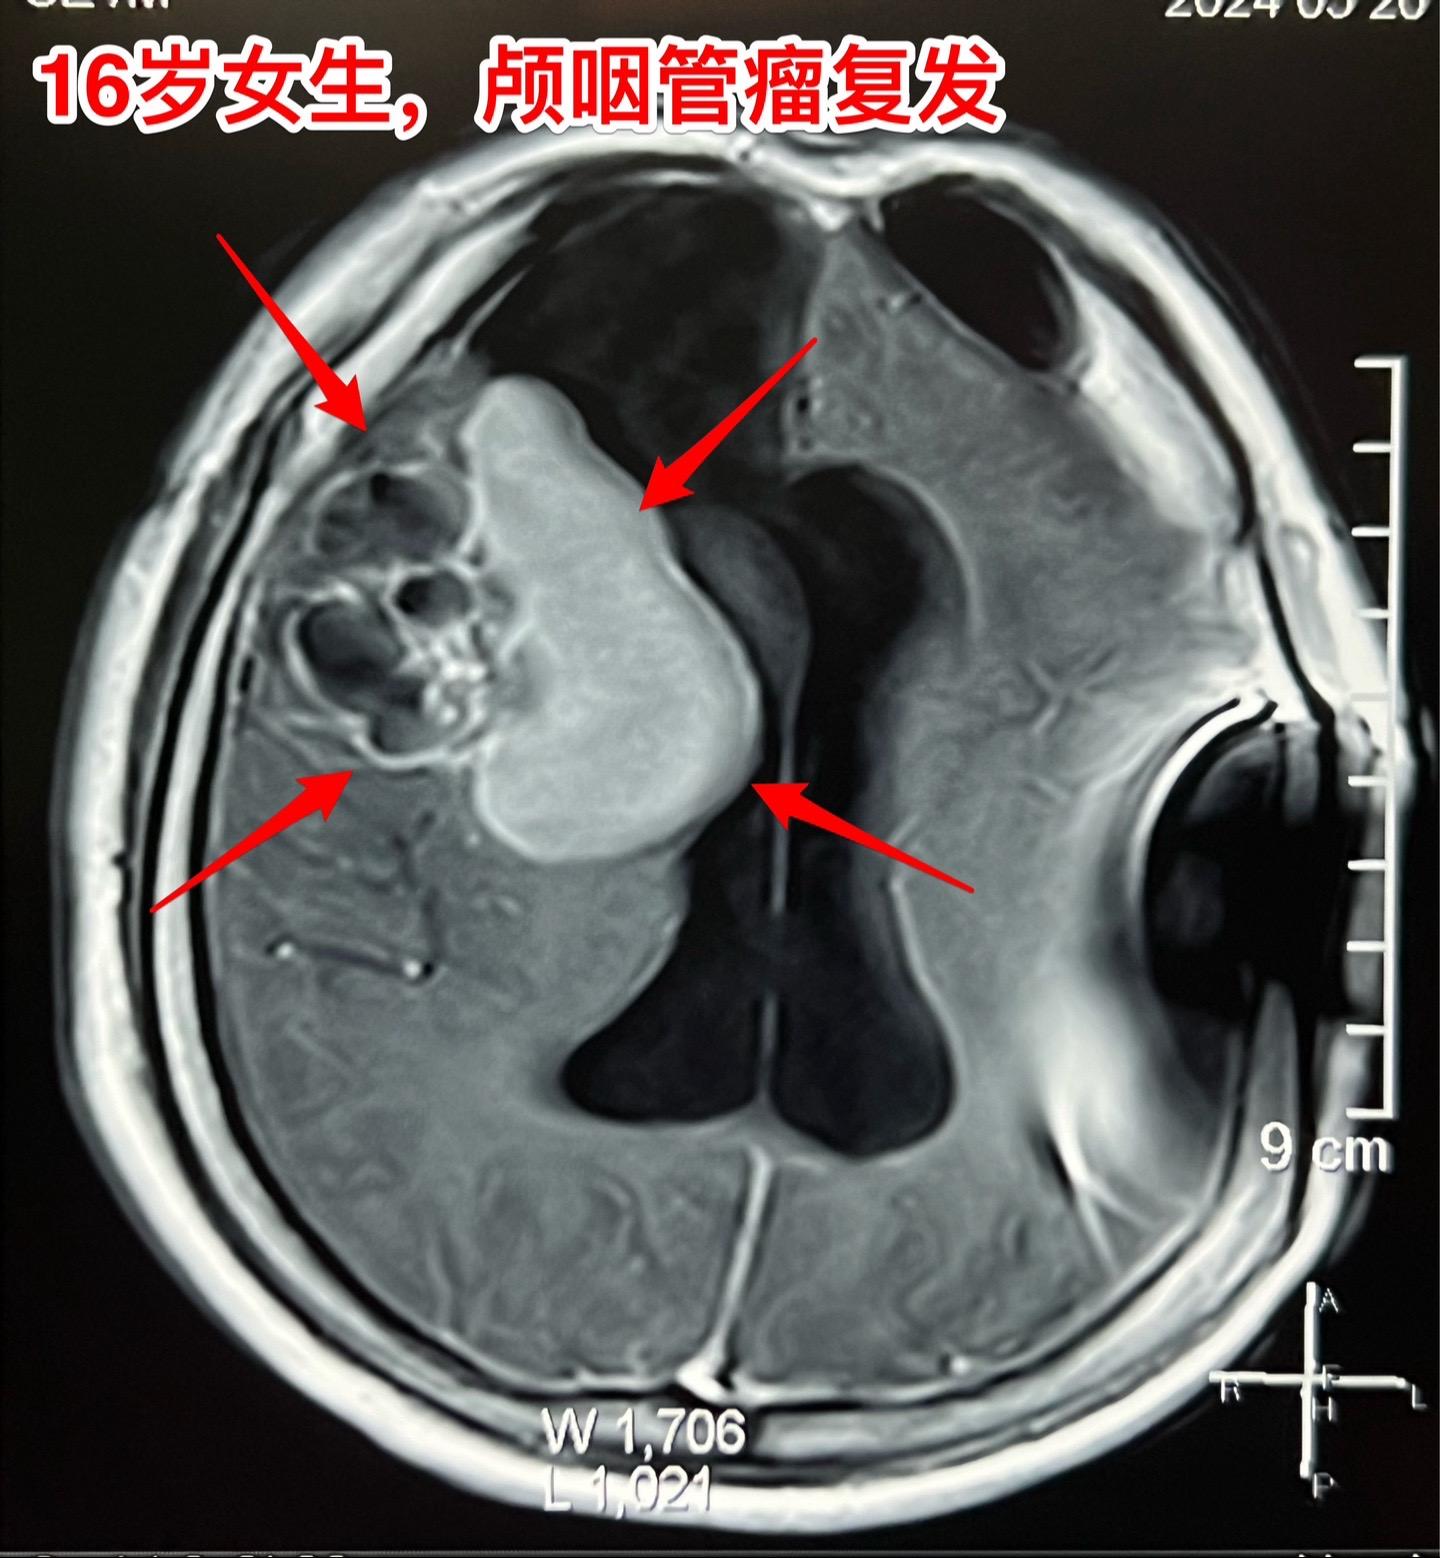

16岁女生颅咽管瘤第三次手术。第二次手术是在2013年1月。那次手术后还因脑积水作了脑室腹腔分流术。出院后能上学读书,而且内分泌方面还不错。有点遗憾的是额部手术疤痕及颅骨变形影响了病人的容貌。 这次的手术原计划在5月28日进行,因为她的生理周期突然提前了(自然的周期)故而将手术推迟到6月4日进行。肿瘤得到完全切除。 这次的肿瘤体积很大,但是还没有影响到垂体-下丘脑,可以预见,她的内分泌功能不会受到破坏。只希望她的肿瘤不再复发。内分泌

16岁女生颅咽管瘤第三次手术。第二次手术是在2013年1月。那次手术后还因脑积水作了脑室腹腔分流术。出院后能上学读书,而且内分泌方面还不错。有点遗憾的是额部手术疤痕及颅骨变形影响了病人的容貌。 这次的手术原计划在5月28日进行,因为她的生理周期突然提前了(自然的周期)故而将手术推迟到6月4日进行。肿瘤得到完全切除。 这次的肿瘤体积很大,但是还没有影响到垂体-下丘脑,可以预见,她的内分泌功能不会受到破坏。只希望她的肿瘤不再复发。颅咽管瘤内分泌